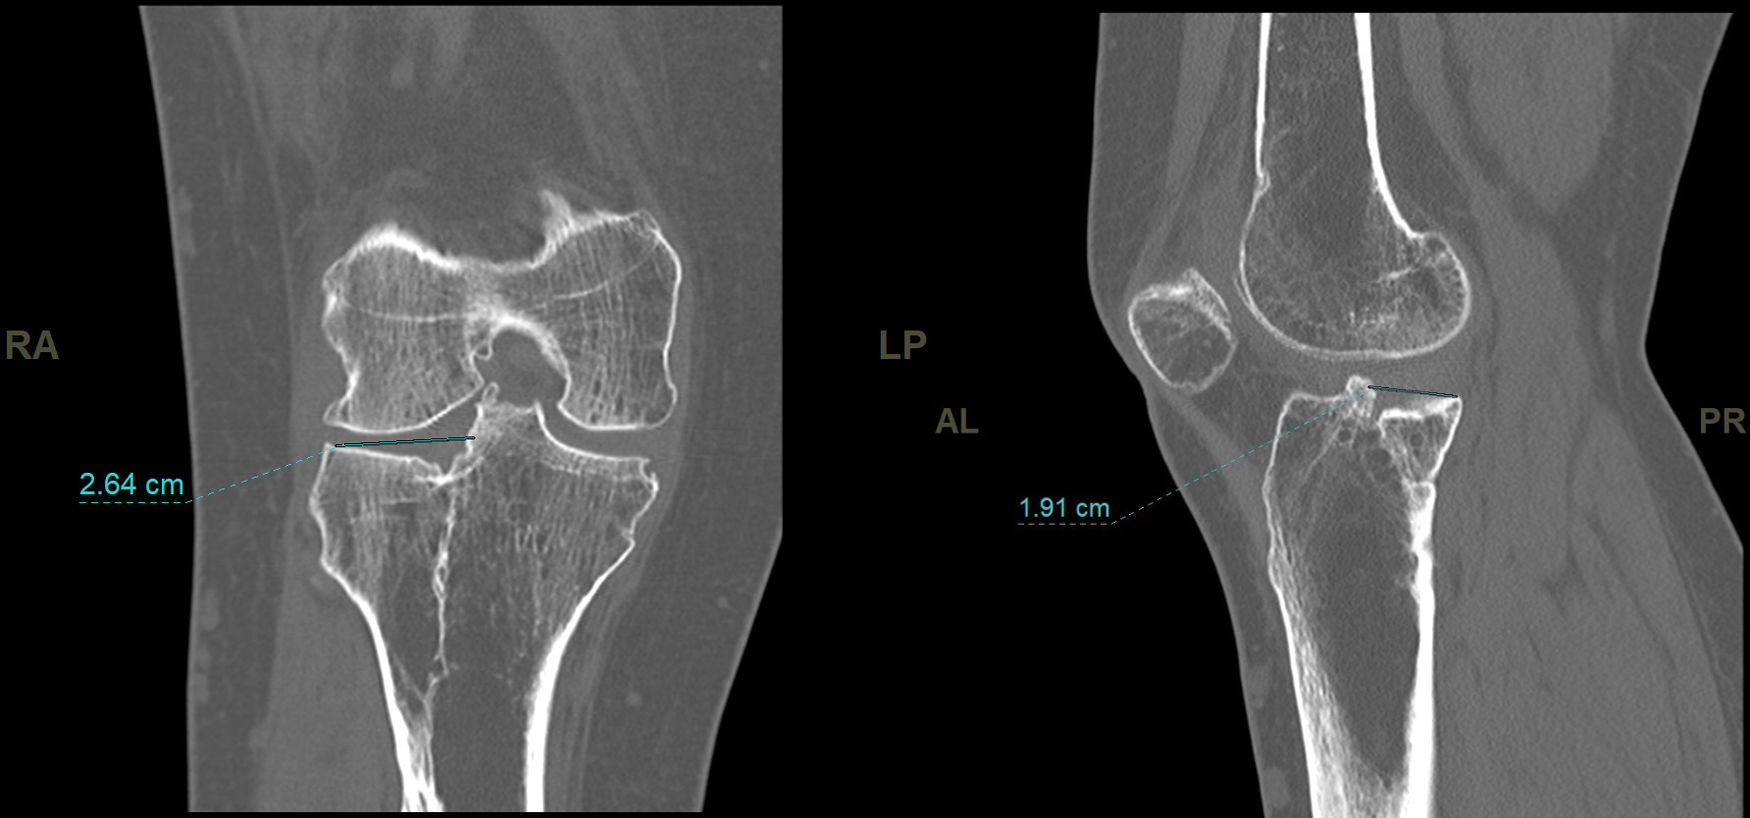

En el estudio de TC se hizo una adquisición volumétrica en un equipo multicorte a 0,6mm con posteriores reconstrucciones multiplanares de 1,5mm de espesor y 1,0mm de intervalo. En la reconstrucción en el plano coronal se analizó el punto de mayor depresión de la fractura en mm que se corresponde con el escalón articular máximo y la anchura máxima/diámetro transversal en mm; en el plano sagital se midió el diámetro máximo anteroposterior en mm del escalón articular y la caída máxima (slope) de la meseta tibial externa en grados (fig. 3). En el post-procesado en el plano axial se delimitó el contorno de la fractura y se calculó el área afecta en cm2, así como el diámetro mayor anteroposterior y la anchura máxima en mm (diámetros máximos anteroposterior y transversal) (fig. 4).

El escalón medio medido en TC fue de 3,6mm (DE: 1,9mm). El área media medida en TC fue de 17,57cm2 (DE: 6,1cm2) El slope medio fue 12,3grados (DE: 5,3grados).

| TAC escalón (mm) | 3,6 | 1,9 | 2,8 | 4,4 | 0,7 | 7,5 |

| TAC diámetro mm | 16,47 | 8,56 | 13,08 | 19,85 | 2,03 | 36 |

| TAC anchura mm | 14,48 | 8,33 | 11,18 | 17,78 | 0,9 | 34,2 |